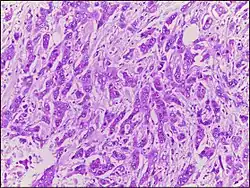

Micrograph of breast tissue with ductal carcinoma. H&E stain. |

Ductal carcinoma is a type of tumor that primarily presents in the ducts of a gland.[1]